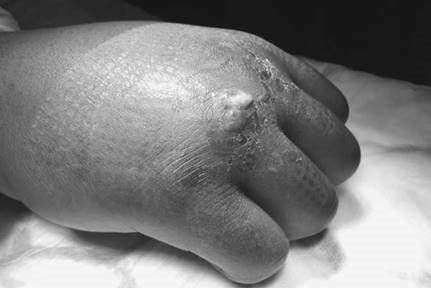

Postoperative complications are broadly categorized into early and late. Early complications include hematoma formation, which is the most common cause of subsequent flap necrosis and deep infection. Meticulous hemostasis prior to closure, use of drains if necessary, and compressive dressings are critical preventative measures. A unique early complication is the "flare reaction," characterized by intense global hand swelling, erythema, and stiffness not caused by infection. This is essentially a localized sympathetic hyperactivity and is treated with aggressive hand therapy, elevation, and a short course of oral corticosteroids.

Late complications are dominated by disease recurrence, joint stiffness, and Complex Regional Pain Syndrome (CRPS). Recurrence is the Achilles heel of Dupuytren’s treatment. The definition of recurrence varies, but it is generally accepted as the reappearance of palpable cords with a progressive contracture >20 degrees in a previously treated ray. Recurrence rates approach 50% at 5 years for regional fasciectomy and are even higher for percutaneous needle fasciotomy. CRPS occurs in roughly 2-5% of patients and presents with out-of-proportion pain, trophic changes, and severe stiffness. Management requires a multidisciplinary approach involving pain specialists, intensive therapy, and occasionally sympathetic nerve blocks.